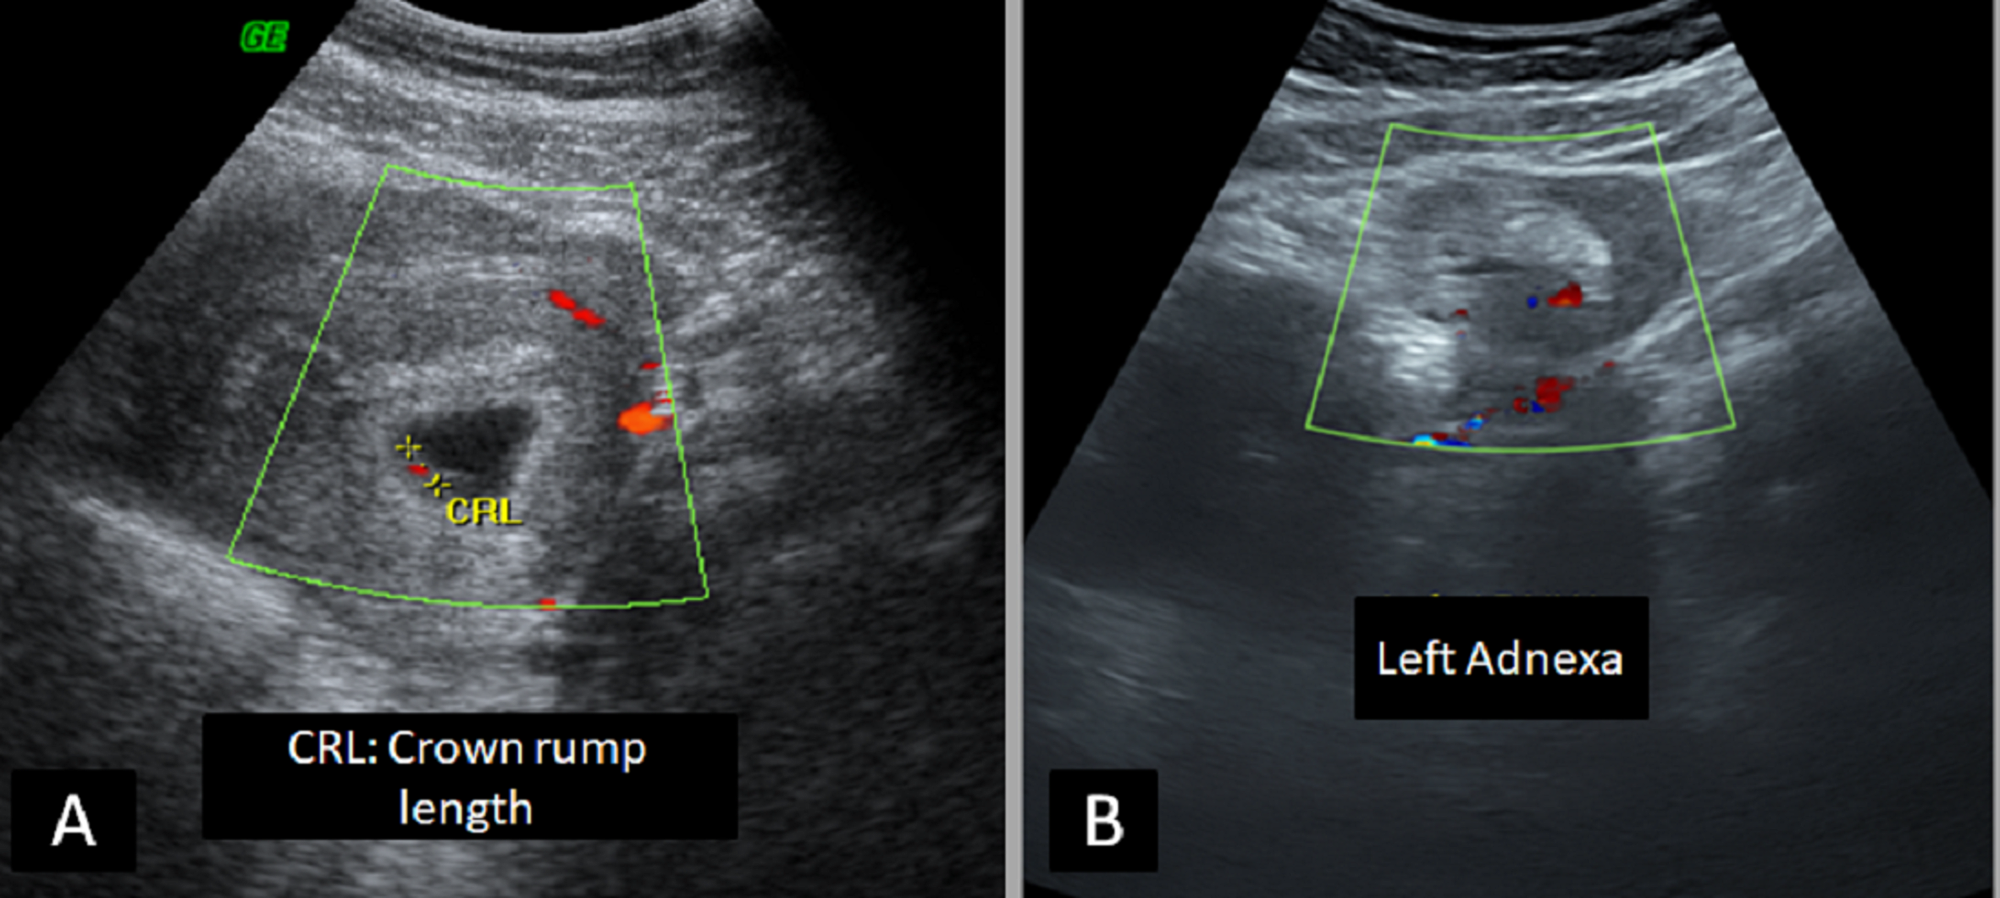

Abstract for heterotopic pregnancy. Heterotopic pregnancy is defined as the coexistence of intrauterine and extrauterine gestation. The course of pregnancy after the surgery was without complications and a healthy baby was delivered at the 39th week of gestation. Heterotopic pregnancy occurs when a patient has simultaneous intrauterine and ectopic pregnancies. The incidence of heterotopic pregnancy is very low.

Hg is commonly identificated when rupture or hemoperitoneum occurs. The diagnosis of hp is still one of the biggest challenges in modern gynecology. Abstract heterotopic pregnancy is the coexistence of living or dead intrauterine pregnancy single or multiple and extrauterine pregnancy located in the oviduct ovary uterine corner cervix or peritoneal cavity. Introduction heterotopic pregnancy hp is defined as the presence of an intrauterine pregnancy iup that coexists with an ectopic pregnancy ep1.

Rates of heterotopic pregnancy have been rising with increased availability and access to in vitro fertilization and other advanced fertility technologies. Hp can occur in several forms eg. When treated properly and on time a heterotopic pregnancy can result in live childbirth with favorable outcomes for both the child and the mother. Symptoms of heterotopic pregnancy are nonspecific such as vague abdominal pain so transvaginal ultrasound is a crucial part of the.